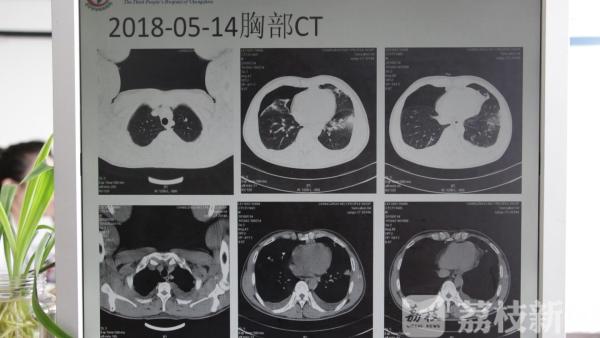

前不久,常州市三院呼吸科的病房收治过两例病情有些奇怪的患者。其中一名患者因为胸闷气喘,来到呼吸科就诊,医生检查后发现,患者的病情并不简单。查了血常规,发现病人嗜酸性粒细胞异常增高,高于正常9倍以上。医生经过询问得知,该患者曾经在老家生吃过一只虾子。经过相关的检查,确定患者为肺吸虫感染。而另外一名患者,也是有着类似的经历。该患者的老家在沿海城市,当地人喜欢吃醉虾醉蟹。该患者有一次回老家时尝了尝鲜,到常州后就发生了胸闷气喘。

两名患者经过对症治疗以后,均已痊愈出院。有人认为,吃鱼虾时,只要加些酒、盐、酱油、醋等佐料,就可杀死寄生虫囊蚴,何况食入后还要经过酸性胃液的消化,生食无妨。但科学家经过多次实验证明,上述方法不能完全杀死寄生虫囊蚴,仍有近一半的囊蚴会存活。如果人们生吃带有寄生虫囊蚴的河鲜海鲜,囊蚴会在人体肠壁上长成幼虫,随后便在人体组织游走入侵脏器。大部分是爬进肺里,也有在胸腔部位造成胸腔积液、心包积液。如果继续向上游走钻入大脑,会诱发癫痫等疾病。由于寄生虫感染引发的症状并不典型,往往会给诊治带来一定的困难。